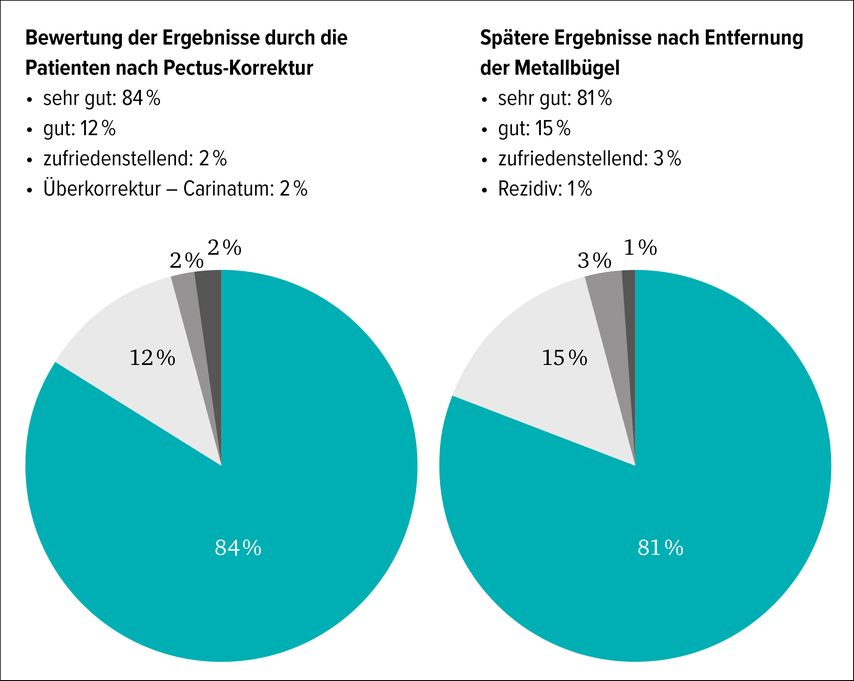

Die Behandlungsresultate sind in über 80% der Patienten als „sehr gut“ beurteilt. Diese Zufriedenheit bleibt auch nach der operativen Implantat-Entfernung bestehen (Abb.9).